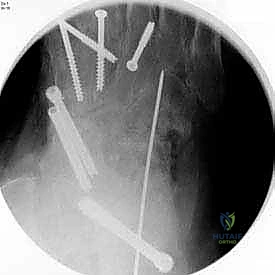

بعد التأكد من الوضعية المثالية للعظام، يتم تثبيتها بقوة باستخدام مسامير معدنية مجوفة من التيتانيوم (Cannulated Screws) أو شرائح معدنية خاصة. يتم إدخال المسامير تحت توجيه الأشعة السينية المباشرة (Fluoroscopy) داخل غرفة العمليات لضمان الدقة المتناهية. هذه المسامير تضغط العظام معاً وتمنع أي حركة حتى يحدث الالتئام التام.